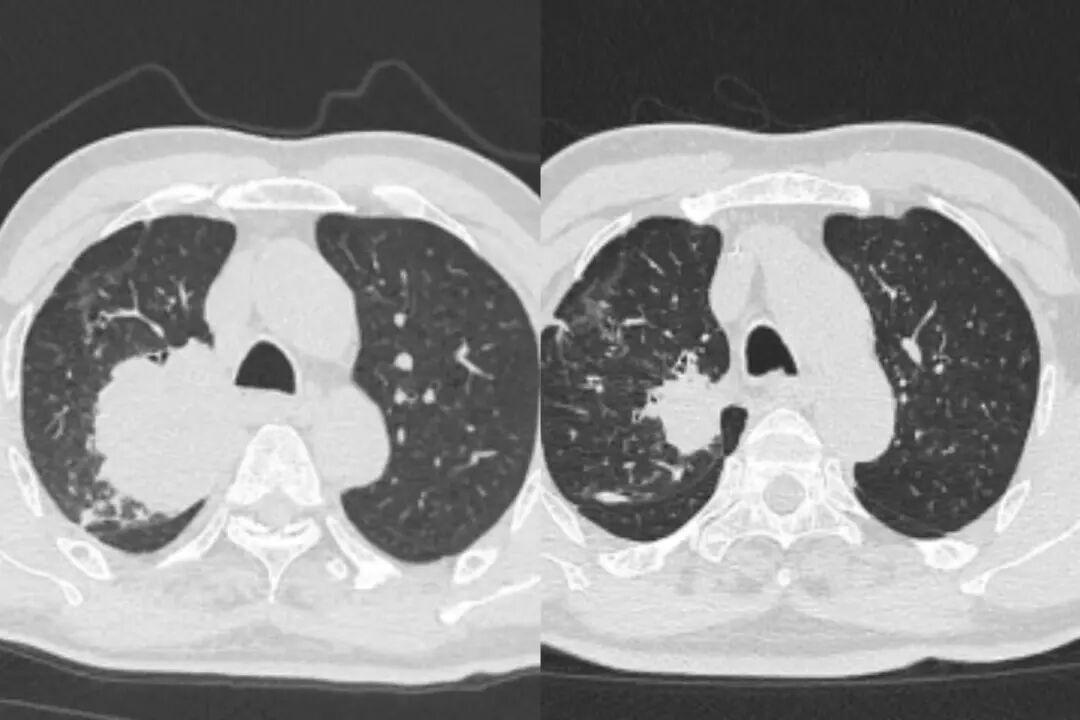

△赵大叔治疗前后CT对比

△钱大叔治疗前后CT对比

pCR,即病理学完全缓解,在肿瘤治疗中是一个金标准式的胜利。它意味着患者在接受术前新辅助治疗后,手术切除的病灶组织中已检测不到癌细胞。对患者而言,代表着他们很可能告别肿瘤,重回正常生活。

最终的病理报告带来了最振奋人心的消息,两人的手术标本均达到了pCR,肿瘤细胞已经消失。

实现pCR,可以说是患者治疗的一个重要节点。李剑锋主任表示,这意味着患者不仅获得了手术的机会,术后也大概率无需再进行放化疗,极大地减轻了身心负担,真正实现了高质量的长久生存。(通讯员 刘裕)